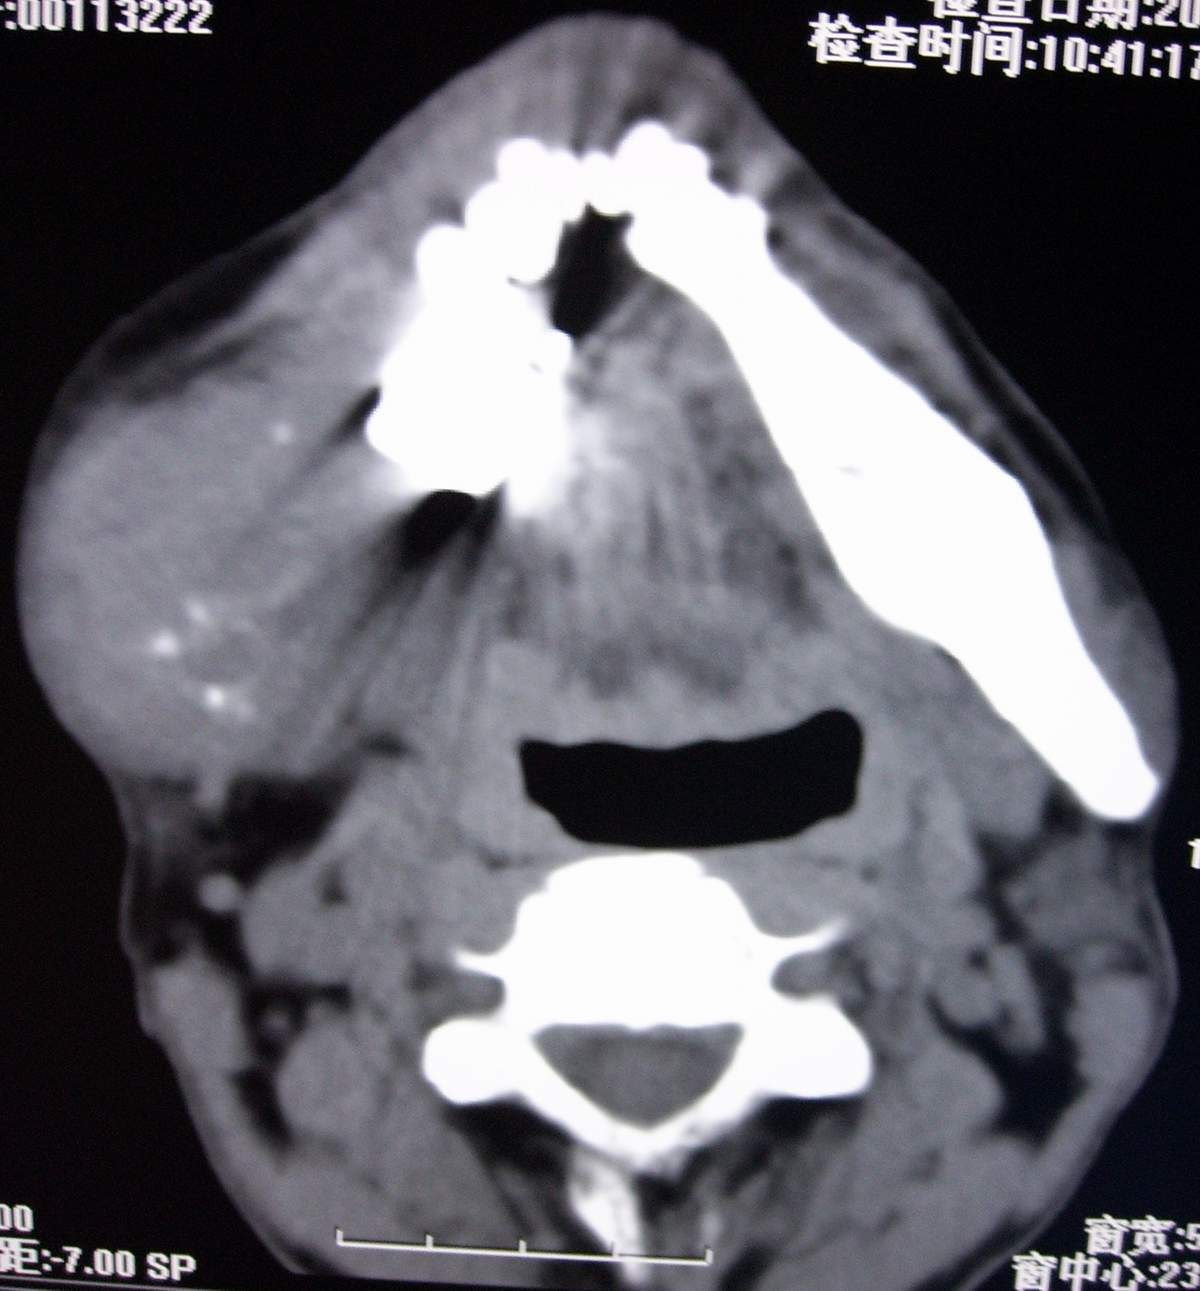

男,54岁,右下颌肿痛1月余。

右侧下颌骨水平部及升支呈溶骨性破坏,无明显膨胀,周围见软组织肿块。

考虑:右侧下颌骨恶性肿瘤或转移瘤。

右下颌骨溶骨性破坏,代之以团块状软组织影,内有斑片状瘤骨,边缘骨质有少量骨膜反应,考虑:右下颌骨骨肉瘤。期待病理。